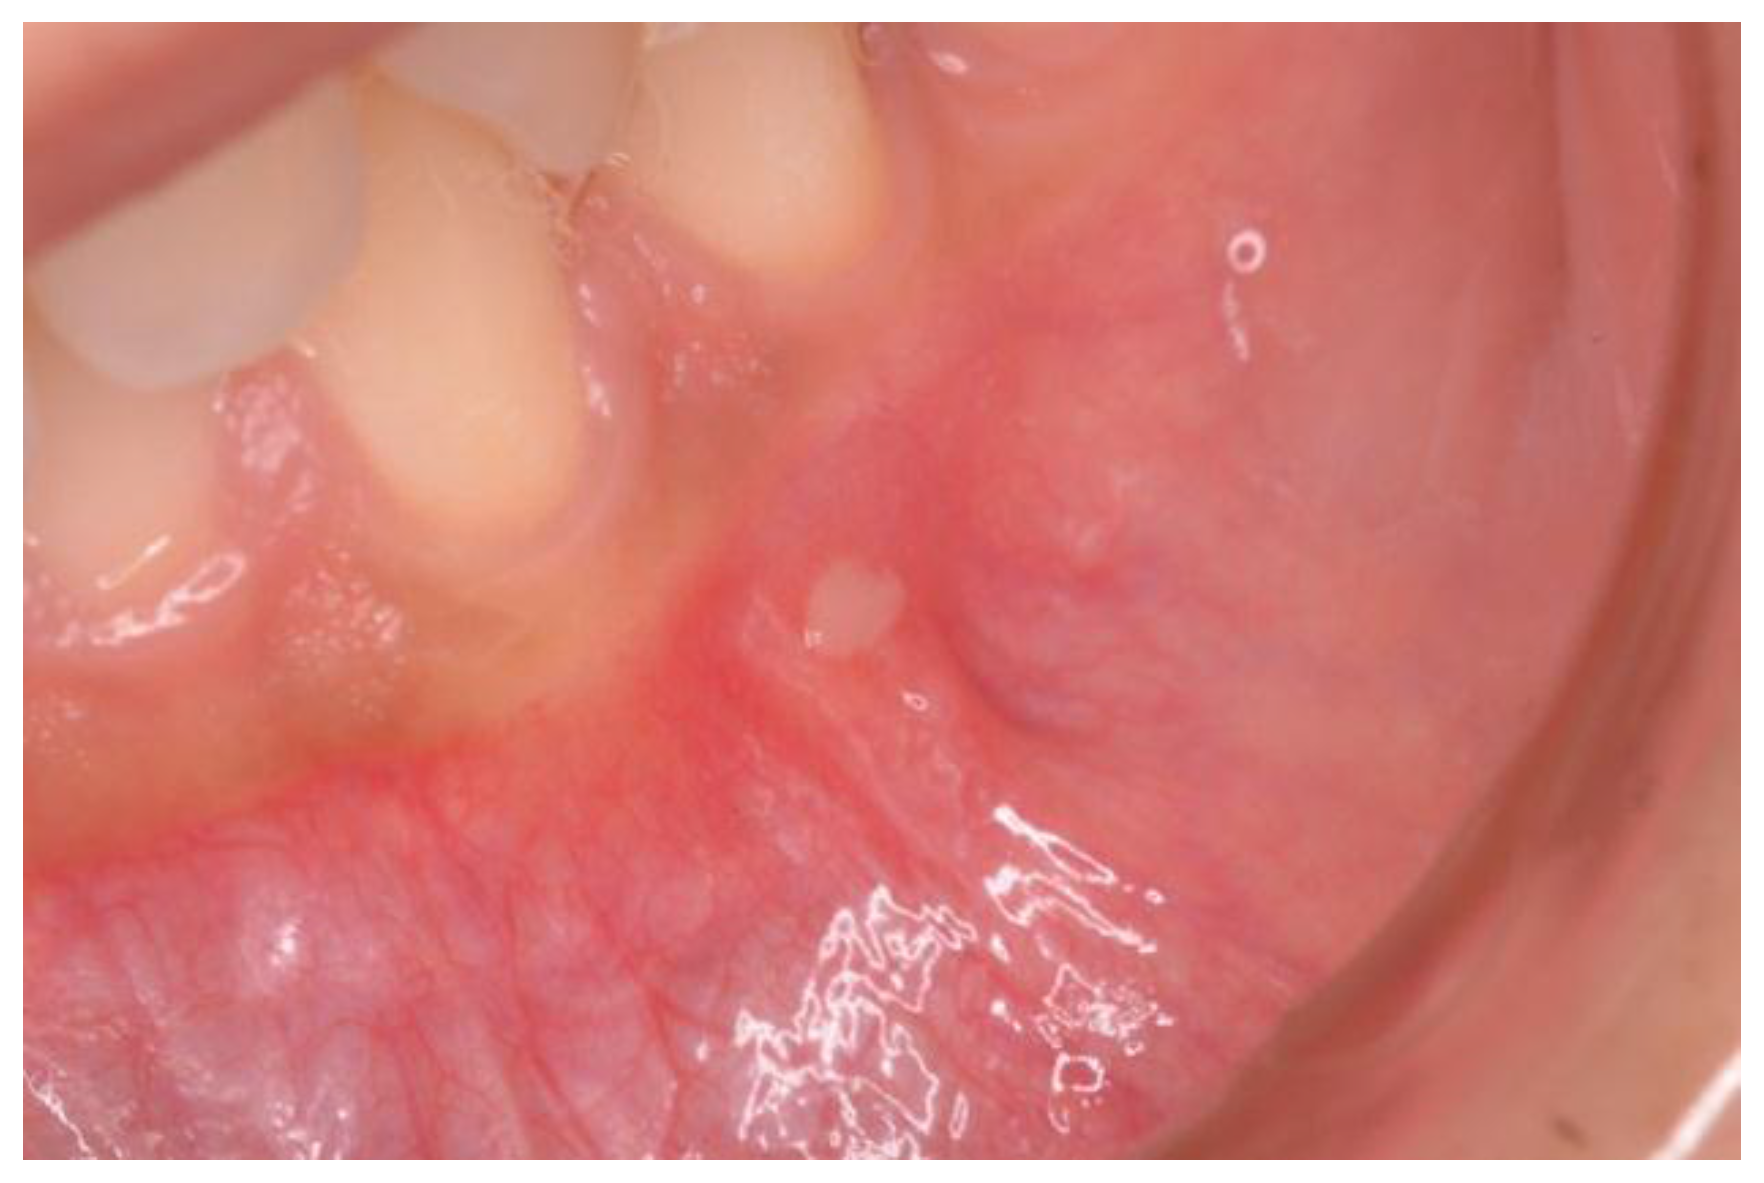

Demographics and clinical information were collected during the gastroenterological visit, and data were recorded in a dedicated database. At the moment of the dental visit, patients were asked about recurrent aphthous stomatitis (RAS) characterized by recurrent bouts of solitary or multiple shallow painful ulcers, at intervals of a few months to a few days in patients who were otherwise well (Figure 1) [12]. Aphthosis at the time of the exam was also detected.

Figure 1. A case of aphthosis on the buccal mucosa.